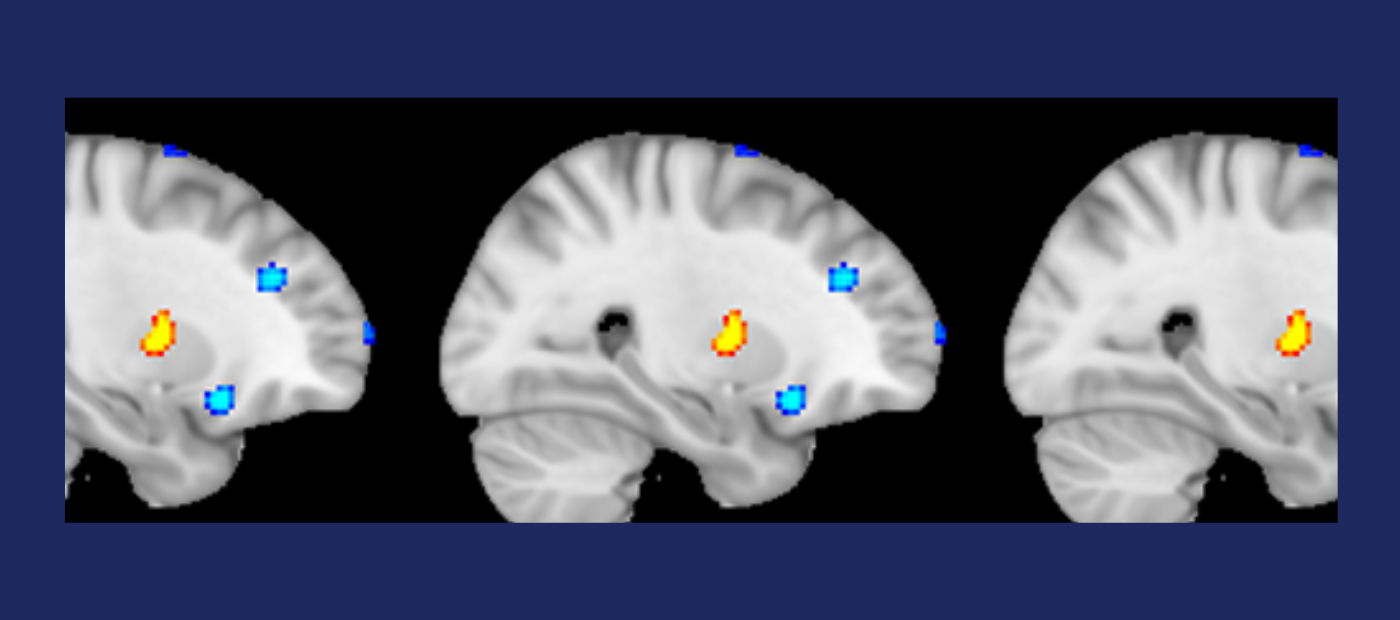

Machine-learning and neuroimaging techniques have been used to accurately distinguish between individuals with Dissociative Identity Disorder (DID) and healthy individuals, on the basis of their brain structure, in new research part funded by the NIHR Maudsley Biomedical Research Centre and published in The British Journal of Psychiatry.

Researchers performed MRI (magnetic resonance imaging) brain scans on 75 female study participants — 32 with independently confirmed diagnoses of DID and 43 who were healthy controls. The two groups were carefully matched for demographics including age, years of education and ancestry.

Using machine-learning techniques to recognise patterns in the brain scans, the researchers were able to discriminate between the two groups with an overall accuracy of 73%, significantly higher than the level of accuracy you would expect by chance.

This research, using the largest ever sample of individuals with DID in a brain imaging study, is the first to demonstrate that individuals with DID can be distinguished from healthy individuals on the basis of their brain structure.